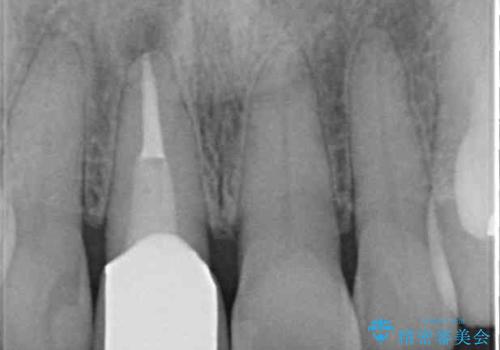

土台に含まれている金属も含め、口腔内の金属は全て除去し、抜歯しなければならない歯は抜歯し、オールセラミッククラウンやセラミックインレーにて治療することとしました。

上下奥歯の抜歯を同時期に行わず、下顎の治療を終えてから上顎を抜歯して治療を進めたため、1年ほどの期間を要しました。

- 根管治療により痛みや腫れがひかない事や、術後に痛みや腫れが生じる事、治療によるファイル破折やパーフォレーションなどの偶発症、術後の歯根破折を生じる可能性もあります